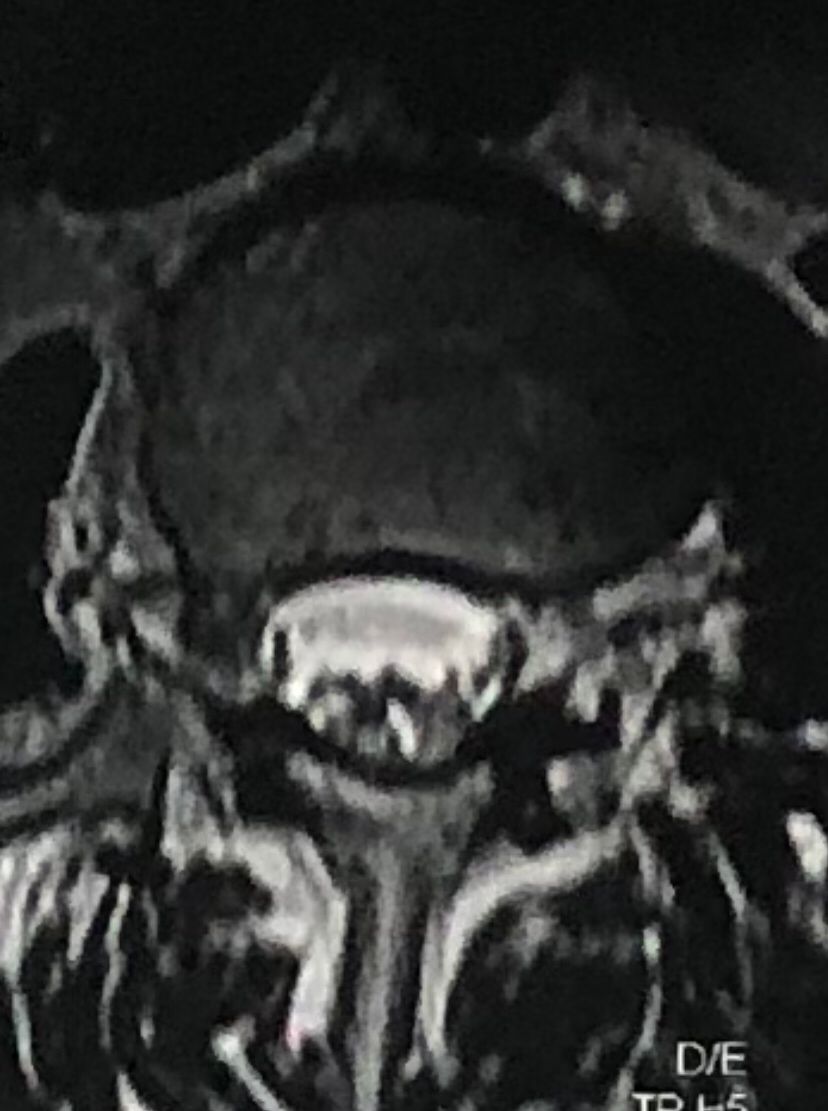

In his MRI was reported R. para R. IVF Massive extrusion. I decided to control his pain and manage this patient with reevaluation of patient every other session. For 5 sessions i just used acupuncture and laser and IFC and mild adjustments to his R. T3-T7 and mild arthosteem to above and below involved segment. Cervical adjustment considered contraindicated for this patient. From session 6th- 8th i started to use mild/gentle cervical decompression. He used soft cervical collar all the time. His pain decreased by 80 percent

I gave him cervical traction pump to be used 3-5 times per day at home for the next 3 months and i released the patient. He was evaluated every week once for one month and after that every 2 weeks. After 3 month I repeated MRI. Size of the herniated disc was reduced greater than 50 percent. Asked him to do another mri in 6 months

MRIs before and after proper management of this patient: